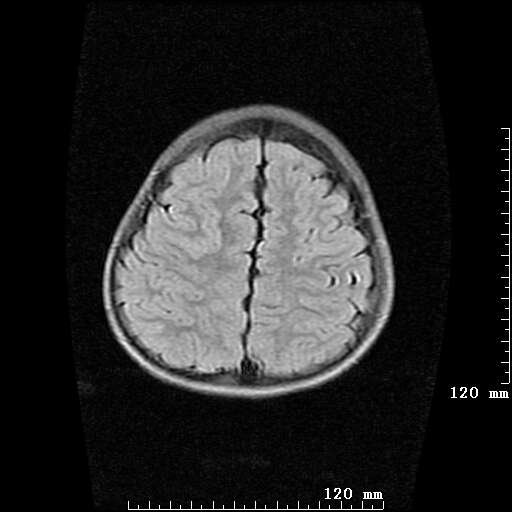

女,7岁,三岁才说话、走路。现智力尚可,走路不稳。临床怀疑大脑发育不全。

考虑 脑白质发育不良

脑折质变薄,双侧侧脑室稍扩张,支持考虑脑折质发育不良

考虑胼胝体发育不全,髓鞘形成不良。

支持考虑胼胝体发育不全,髓鞘形成不良。

侧脑室周围白质数量减少,侧脑室不对称性扩大,左侧侧脑室后角呈方形改变,脑沟加深,结合临床考虑脑室周围白质软化症(pvl)。期待结果!

支持脑白质发育不良。